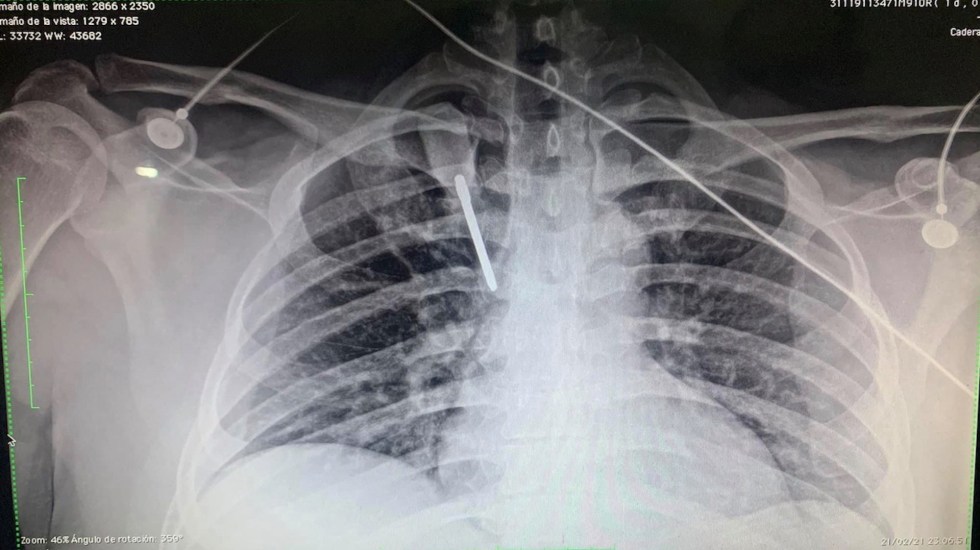

Tras el atraco, los dos sujetos le clavaron en el pecho a Soria un desarmador.

Después de esto, los agresores huyeron del lugar mientras equipos de emergencia atendieron al médico residente.

El médico detalló que continúa con vida gracias a la atención de un equipo médico y a que recibió atención oportuna.